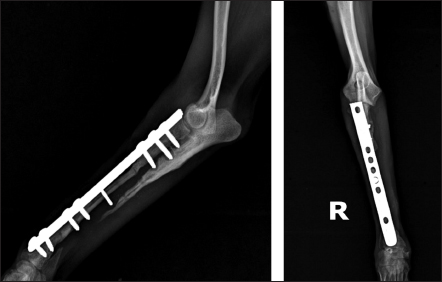

Fig. 4. Mediolateral and craniocaudal radiographs of antebrachial bones, 9 weeks after the revision surgery showing very good cortical graft bridging.

Fig. 5. Left—mediolateral radiograph of antebrachial bones 12 weeks after the revision surgery after the removal of screws from the cortical autograft; Right—mediolateral radiograph by the 15th week demonstrating complete union of the radial fracture and bone callus remodeling.

During the control examination by the 9th post-operative week, the weight bearing with the limb was steady, whereas lameness, pain, and swelling were absent. Radiologically, an excellent bridging of the cortical graft without loosening of fixation implants was demonstrated (Fig. 4).

After the second control examination by the 12th post-operative week, because of the good radiological and clinical outcome, the three screws in the cortical graft were removed, leaving only screws in the proximal and distal bone fragments. By the 15th week, due to excellent clinical outcomes, all implants were removed (Fig. 5).